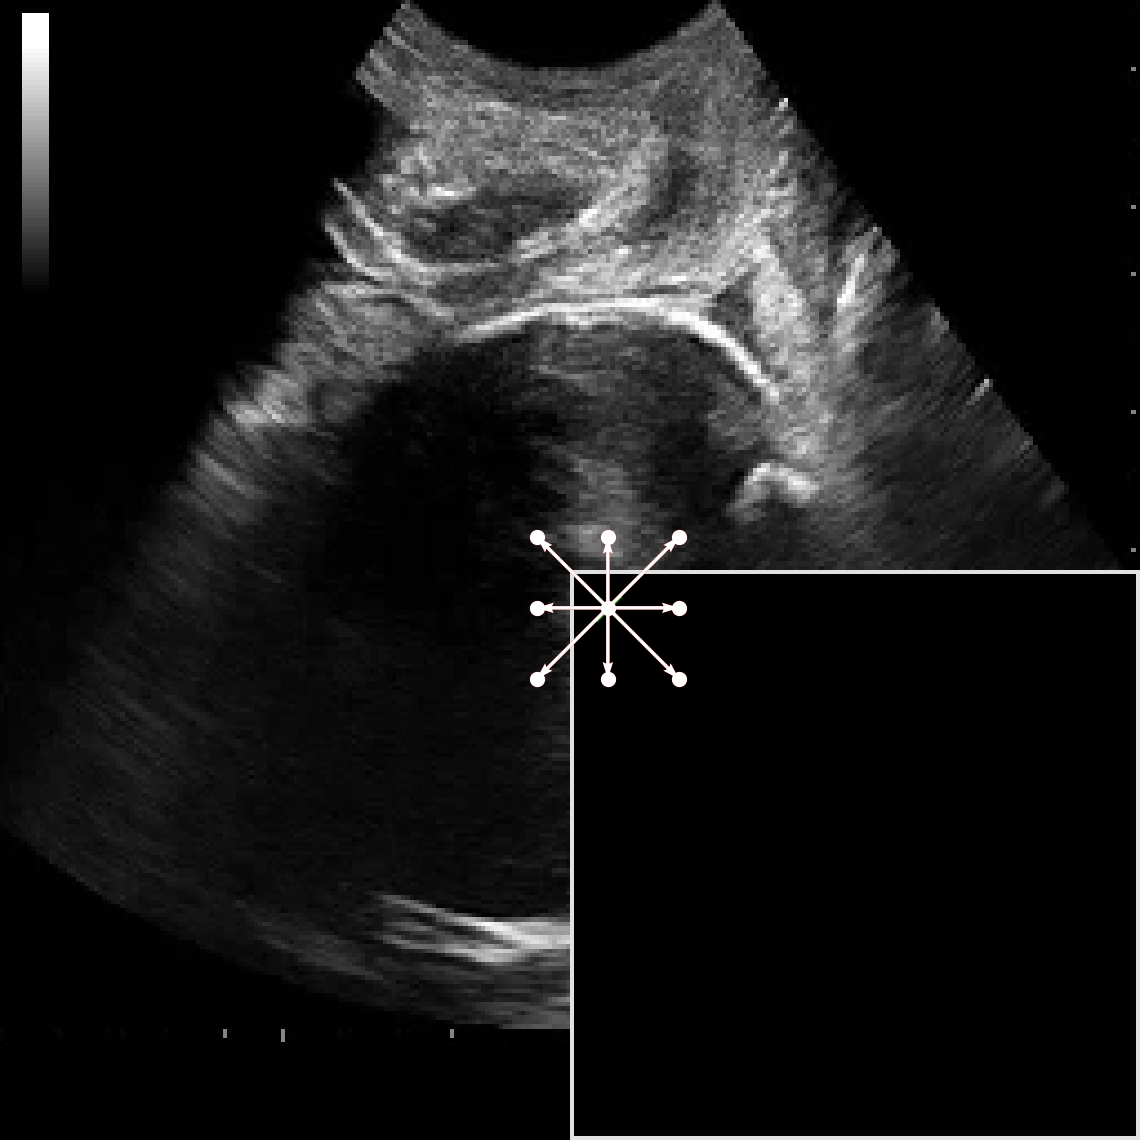

In practical clinical settings, medical images are often incomplete or degraded due to occlusions, artifacts, or limited fields-of-view. Therefore, a reliable segmentation model must be robust to missing spatial context and capable of inferring anatomical structures from partially observed inputs. To evaluate this critical property, we conducted a masking experiment using the FH-PS-AoP dataset. In this experiment, we systematically removed one quadrant from the input image, top-left, top-right, bottom-left, or bottom-right, and evaluated the performance of DAUNet compared to the baseline UNet.

Figure 7 presents a comprehensive visual comparison of the predicted offset maps and segmentation masks under each masking condition. The first column shows the original (unmasked) input along with its corresponding predictions, while subsequent columns depict the results for each of the masked quadrants.

DAUNet demonstrates markedly higher resilience to missing context compared to UNet. Its predicted offset maps remain dense and structured, with vectors that preserve anatomical directionality even when significant regions of the input are absent. This behavior reflects DAUNet’s ability to infer context from the remaining visual cues. In contrast, UNet exhibits sparse or disoriented offsets in the masked scenarios, indicating reduced spatial awareness and compromised localization.

To better understand this phenomenon, we analyzed the receptive fields of both models. For a representative pixel, we visualized its corresponding receptive area contributing to the output. In UNet, the receptive field is fixed and grid-constrained (refer to second row of Figure 7), making it sensitive to occlusions. On the other hand, DAUNet leverages deformable convolutions to dynamically adjust its receptive field based on the visible content. This adaptability is evident in the red and white arrows in the fourth column of Figure 7, where DAUNet modifies its offset patterns to account for the masked input.

The segmentation masks in third and fourth rows of Figure 7, further substantiate these findings. DAUNet consistently produces anatomically plausible segmentations of both the fetal head (green) and pubic symphysis (red), with minimal degradation even under 25% missing input. The output contours remain smooth, accurate, and well-aligned with ground truth boundaries. In contrast, UNet’s performance deteriorates noticeably, with fragmented or distorted segmentations, especially around the fetal head, as indicated by white arrows in the figure.

These results highlight the efficacy of DAUNet’s architectural innovations. The combination of deformable convolution and SimAM attention allows the model to effectively reason over the visible context and compensate for spatial omissions. This robustness to incomplete inputs makes DAUNet well-suited for deployment in real-world medical environments, where noise, occlusions, and partial data are common challenges.